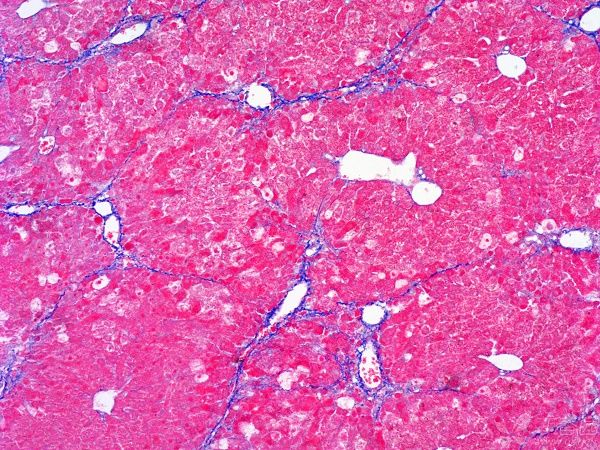

MASSON染色實驗的目的是為了在組織學研究中可視化并區(qū)分不同類型的纖維,特別是膠原纖維和肌纖維。MASSON染色實驗目的由普拉特澤生物病理染色平臺總結(jié)分享,病理組織染色平臺為廣大科研實驗人員提供MASSON染色實驗服務,先一起來學習學習關于MASSON染色實驗目的

這種染色方法通過特定的化學反應和染料選擇,使得不同類型的纖維在顯微鏡下呈現(xiàn)出不同的顏色,從而便于研究者對組織結(jié)構(gòu)和病變進行準確的觀察和分析。

㈠:MASSON染色通過特定的染色劑:能夠使膠原纖維和肌纖維分別呈現(xiàn)出不同的顏色,從而實現(xiàn)對這兩種重要組織成分的精準區(qū)分。這對于后續(xù)的組織學研究具有非常重要的意義。

㈡展示組織纖維化程度:作為一種重要的組織纖維化觀察方法,MASSON染色能夠清晰地顯示出組織中的纖維結(jié)構(gòu),包括膠原纖維的排列、形態(tài)和數(shù)量等。通過對這些信息的觀察和分析,研究人員可以準確地評估組織的纖維化程度,為進一步的研究和治療提供重要依據(jù)。